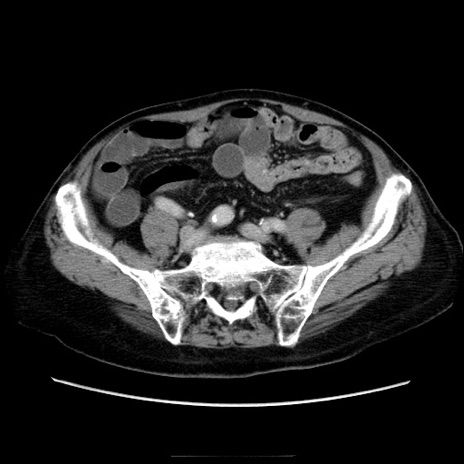

症例21(横断像)

【症例】70歳代男性

【主訴】腹痛

【現病歴】肝硬変・肝細胞癌にてかかりつけの方。約9時間前に食後より腹痛出現。症状が徐々に増悪し、嘔吐出現したため来院。

【既往歴】肝硬変、肝細胞癌(RFA、TACE後)

【身体所見】意識清明、表情苦悶様、BT 36℃、BP 129/78mmHg、P 88bpm、SpO2 97%(RA)、右上腹部から心窩部にかけて圧痛あり、反跳痛なし、筋性防御あり。

【データ】WBC 5800、CRP 0.16